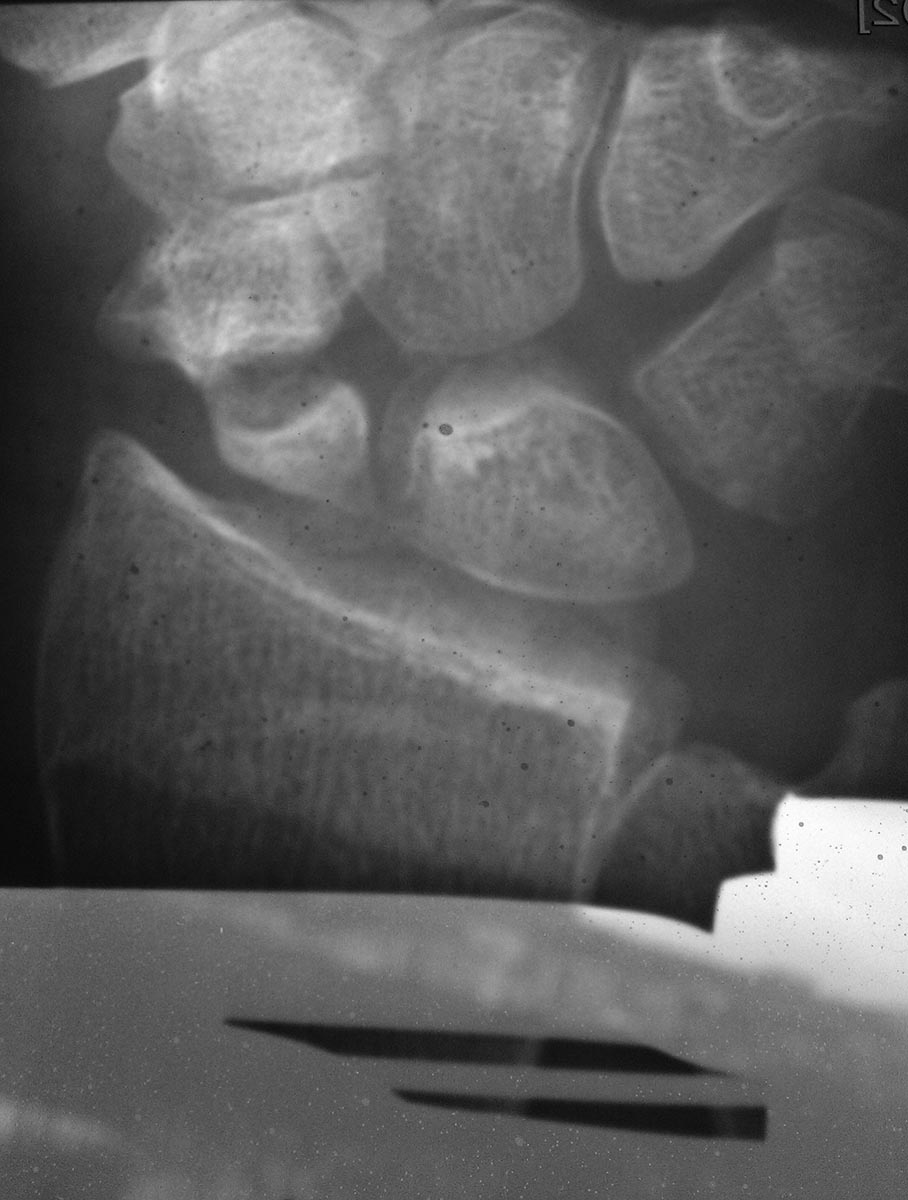

Снимок от 18.03.16 после закрытой репозиции на аппарате Илизарова.

Свежего перелома не вижу. Есть несросшийся перелом ладьевидной кости. Также артроз л/зап. сустава уже есть, видимо травма старинная.

перелом явно старый, более 1 года. Сформировался ложный сустав, есть признаки артроза. Учитывая молодой возраст, возможно стоит рассмотреть остеосинтез винтами Герберта с костной аутопластикой. Надо зачистить шип на ладье, возможно удалить верхушку шиловидного отростка лучевой кости. Еще- в плане личного восприятия- снимки и репозиция все-таки делаются В АППАРАТЕ, а не НА.

Ложный сустав ладьевидной кости не вызывает сомнений, причём до 4.02.2016 - без клинической манифестации. 4.02.2016-травма и подвывих на уровне ложного сустава.

Прошу прощения за возможно резкий тон в моем предыдущим ответе. Судя по снимкам, имеет место ложный сустав ладьевидной кости. Требуется костная пластика перелома и стабильная его фиксация компрессионным канюлированным headless винтом.